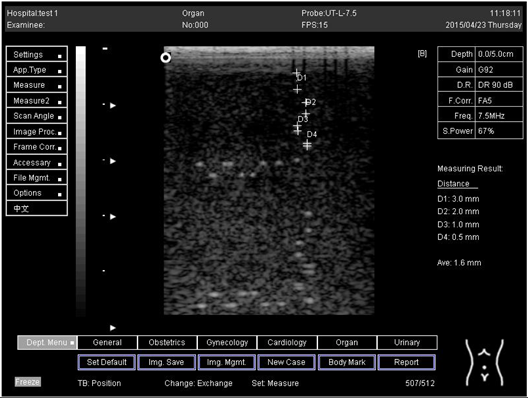

5.0Axial resolution

Biomimetics 07 00130 i011

D1 = 3.0

D2 = 2.0

D3 = 1.0

D4 = 0.5

5.0 Lateral resolution

Biomimetics 07 00130 i012